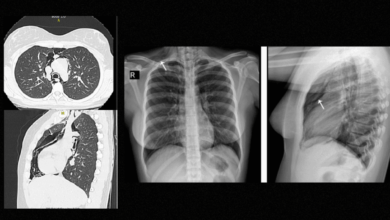

diagnóstico de neumomediastino en una paciente con crisis asmática

El neumomediastino es una entidad poco frecuente, con una prevalencia de 1 caso por cada 7,000 a 44,000 ingresos…